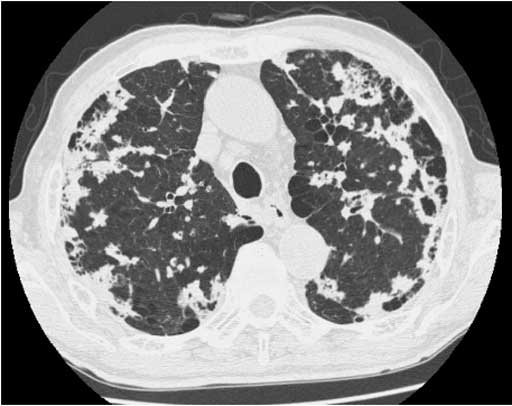

図1 胸部正面単純X線写真 図2 Thin-slice CT1

図2 Thin-slice CT1 図3 Thin-slice CT 2